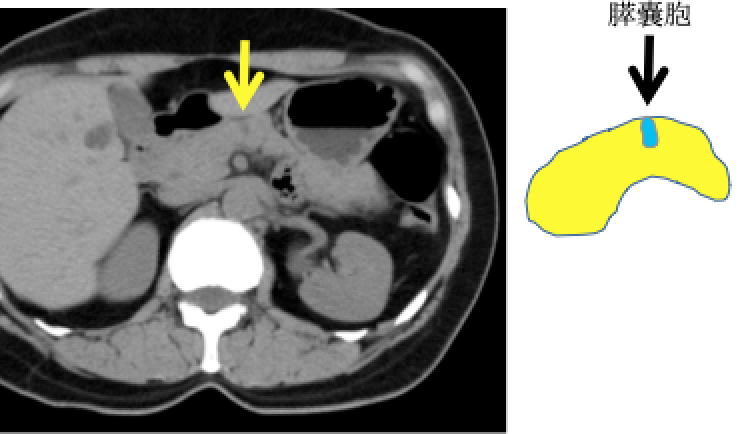

膵臓がんはすい管(消化液〈=すい液〉の通り道)から発生する膵管がんと言われています。 膵臓がんを発症すると、すい管が狭くなり、膵液が停滞します。その際に、主膵管拡張・膵のう胞(分枝膵管拡張)・脂肪変性(膵臓の凹みや痩せ)・腫れといった変化を引き起こします(膵臓がんの間接所見)。これにともなって、膵臓の炎症を起こしたり(みぞおちの痛み)、膵臓のはたらきが低下します(糖尿病の発症や悪化、味覚の変化、下痢など)。顕微鏡レベルの膵臓がん(上皮内がん)でも上記の間接所見や症状を伴うものがあることがわかってきました。膵臓がんが発生してから転移するまで約7年かかると言われております。この間に膵臓の形や膵管の変化をとらえることで早期の膵癌が発見できる可能性があります。

② 膵のう胞